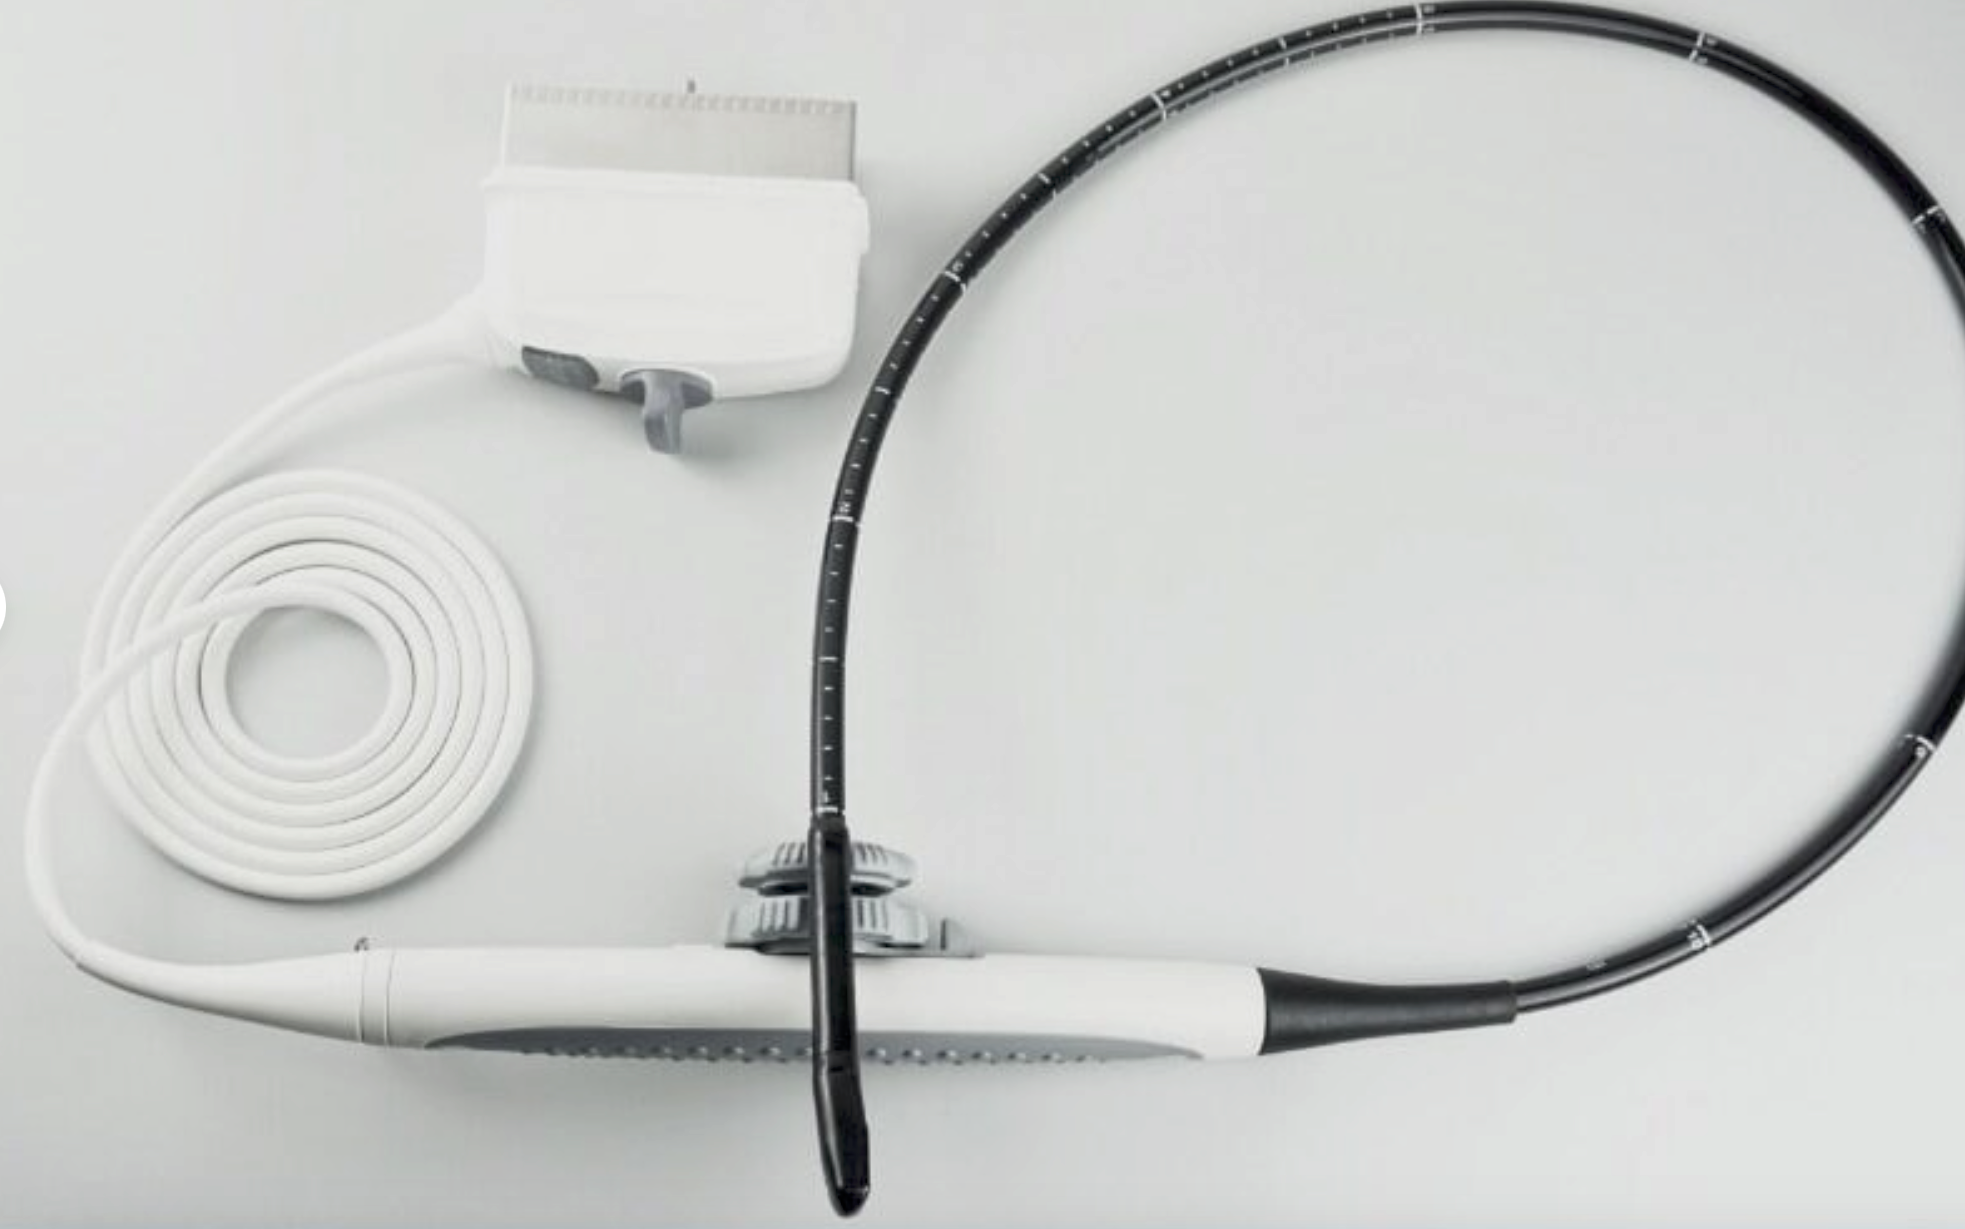

Pro Digital Laptop Ultrasound Machine Linear Array Probe + Transvaginal Probe

The included linear array probe provides high-resolution imaging, ideal for musculoskeletal, vascular, and soft tissue imaging. It delivers clear, detailed images for accurate diagnostics in various applications. The transvaginal probe is designed for internal imaging, offering clear visualization of the female reproductive organs, making it ideal for gynecological exams such as early pregnancy assessments and pelvic evaluations.